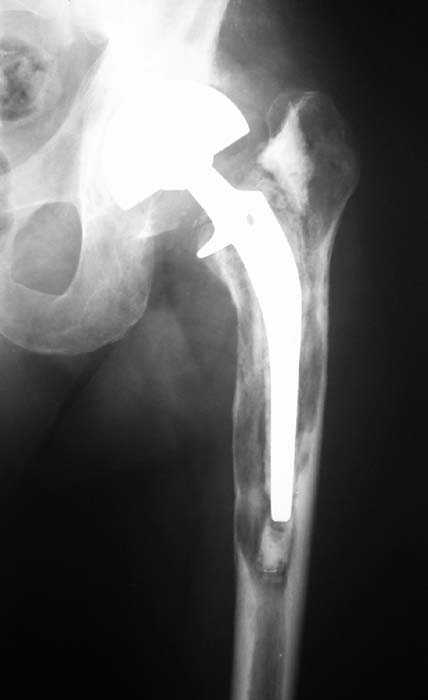

Мужчина, 39 лет.По поводу двустороннего асептического некроза головок бедренных костей последовательно выполнено тотальное эндопроезирование левого (1998 г), затем правого (1999 г) тазобедренных суставов.

С 2001 г отмечает нарастающие боли в левом бедре. Предполагается удаление протеза, удаление цемена из канала бедра, пластика дефекта бедренной кости.

Вторым этапом - тотальное бесцементное протезирование. Ваши предложения, мнения?

Нет никакого смысла делать операцию в два этапа. С чашкой все понятно - стандартный подход с установкой пресс-фит компонента. На бедре имеет

место перипротезный перелом В3 типа - т.е. перелом вокруг ножки с ее нестабильностью на фоне выраженного остеолиза. Решение - доступ к каналу

через перелом с удалением самой ножки, костного цемента и рубцовых тканей. Установка ножки дистальной фиксации (типа Solution), длину ножки

надо определить по шаблону. Минимальный контакт ножки с интактной костью - 6-8 см. Фрагменты проксмального отдела собираются на ножке

эндопротеза, дефекты костной ткани заполняются чипсами (аллографт) и фиксируются кортикальными аллографтами, уложенными дополнительно по типу

"вязанки хвороста" серкляжом. Мы имеем 8 или 10 подобных наблюдений и результатами довольны.